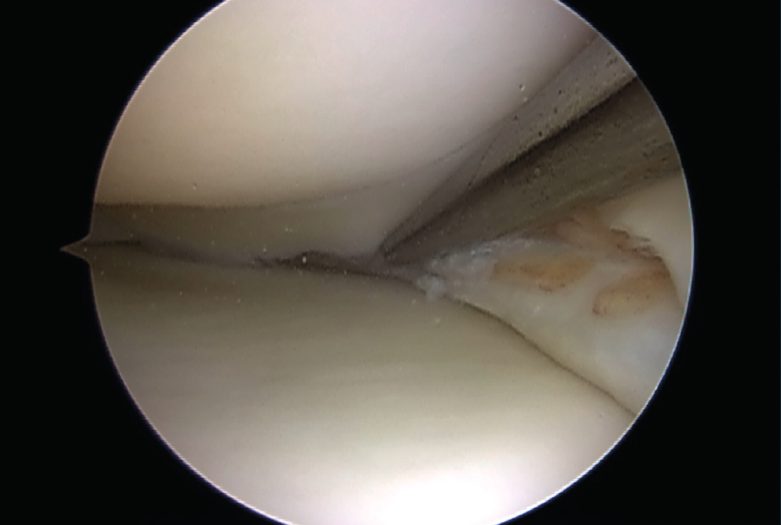

Las roturas periféricas verticales y longitudinales han demostrado buena capacidad para cicatrizar (72 al 94% reportado). Las roturas reparadas en las zonas roja-roja o roja-blanca conducen a buenos y excelentes resultados clínicos a medio plazo. Como guía aproximada, tales desgarros reparables incluyen aquellos a menos de 4 mm del borde meniscal(9)(Figura 3).

Figura 3. Reducción de una rotura en asa de cubo.